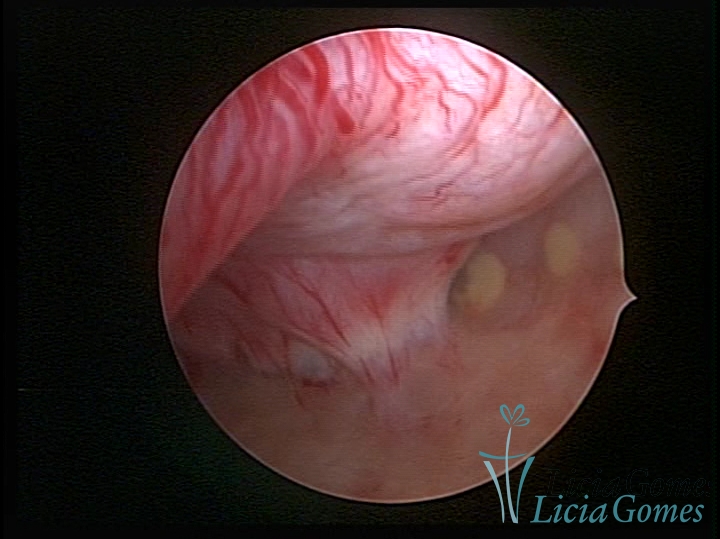

SINÉQUIA TIPO MUCOSA